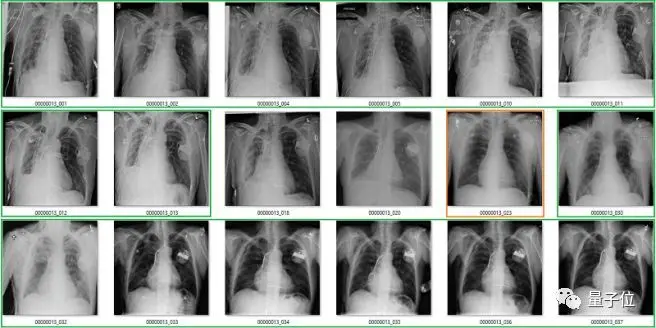

算法是用ChestX-ray14数据集来训练的,这是目前最大的X光数据库,有超过11万张正面胸片,来自3万多位患者。

14,就代表这些胸片里,总共包含了14种肺部疾病。

每一张胸片都要标注,是根据医生的放射学报告,用自动提取 (Automatic Extaction) 的方法来标注的。